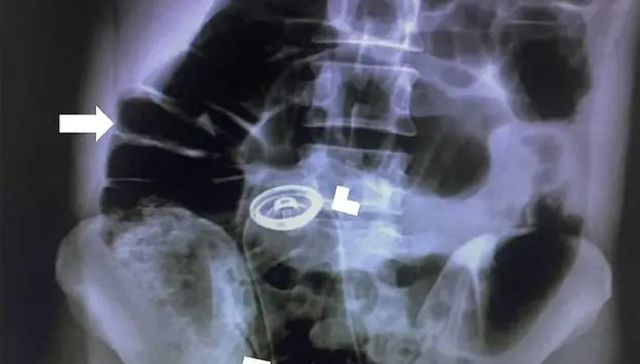

Enfermedad del pene enterrado: qué es y cómo tratarla

Por The New York Times